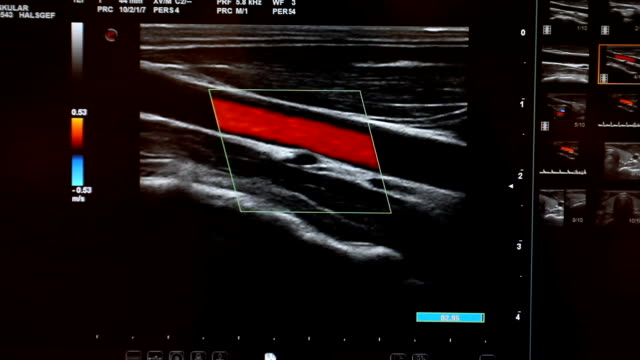

경동맥 초음파 검사의 원리

경동맥 초음파 검사는 초음파 기계를 사용하여 경동맥의 상태를 확인하는 검사입니다. 이 검사는 무해하고 비침습적이며, 빠르게 수행할 수 있어 환자에게 불편함을 주지 않습니다. 검사 과정은 다음과 같습니다.

- 환자는 안정된 자세로 앉거나 누워서 검사를 받습니다.

- 의사나 초음파 기술자는 초음파 젤을 사용하여 목 부위에 초음파 프로브를 적용합니다.

- 초음파 프로브는 고주파 소리파장을 방출하여 경동맥의 이미지를 생성합니다.

- 이미지를 컴퓨터 모니터에 표시하여 의사가 경동맥의 상태를 시각적으로 확인할 수 있습니다.

- 혈류 속도: 혈액이 경동맥을 흐르는 속도를 측정하여 혈액순환에 이상이 없는지 확인합니다.